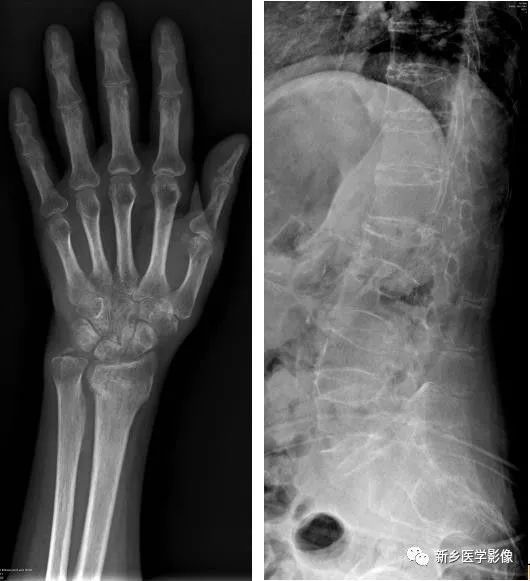

骨质疏松X线图像

a. 手腕部正位示桡骨远段骨折后废用性骨质疏松;b. 腰椎侧位示老年性骨质疏松。

表现为质密度降低,与周围软组织对比度下降。皮质变薄,骨小梁稀疏。腰椎体变扁,呈双凹状。